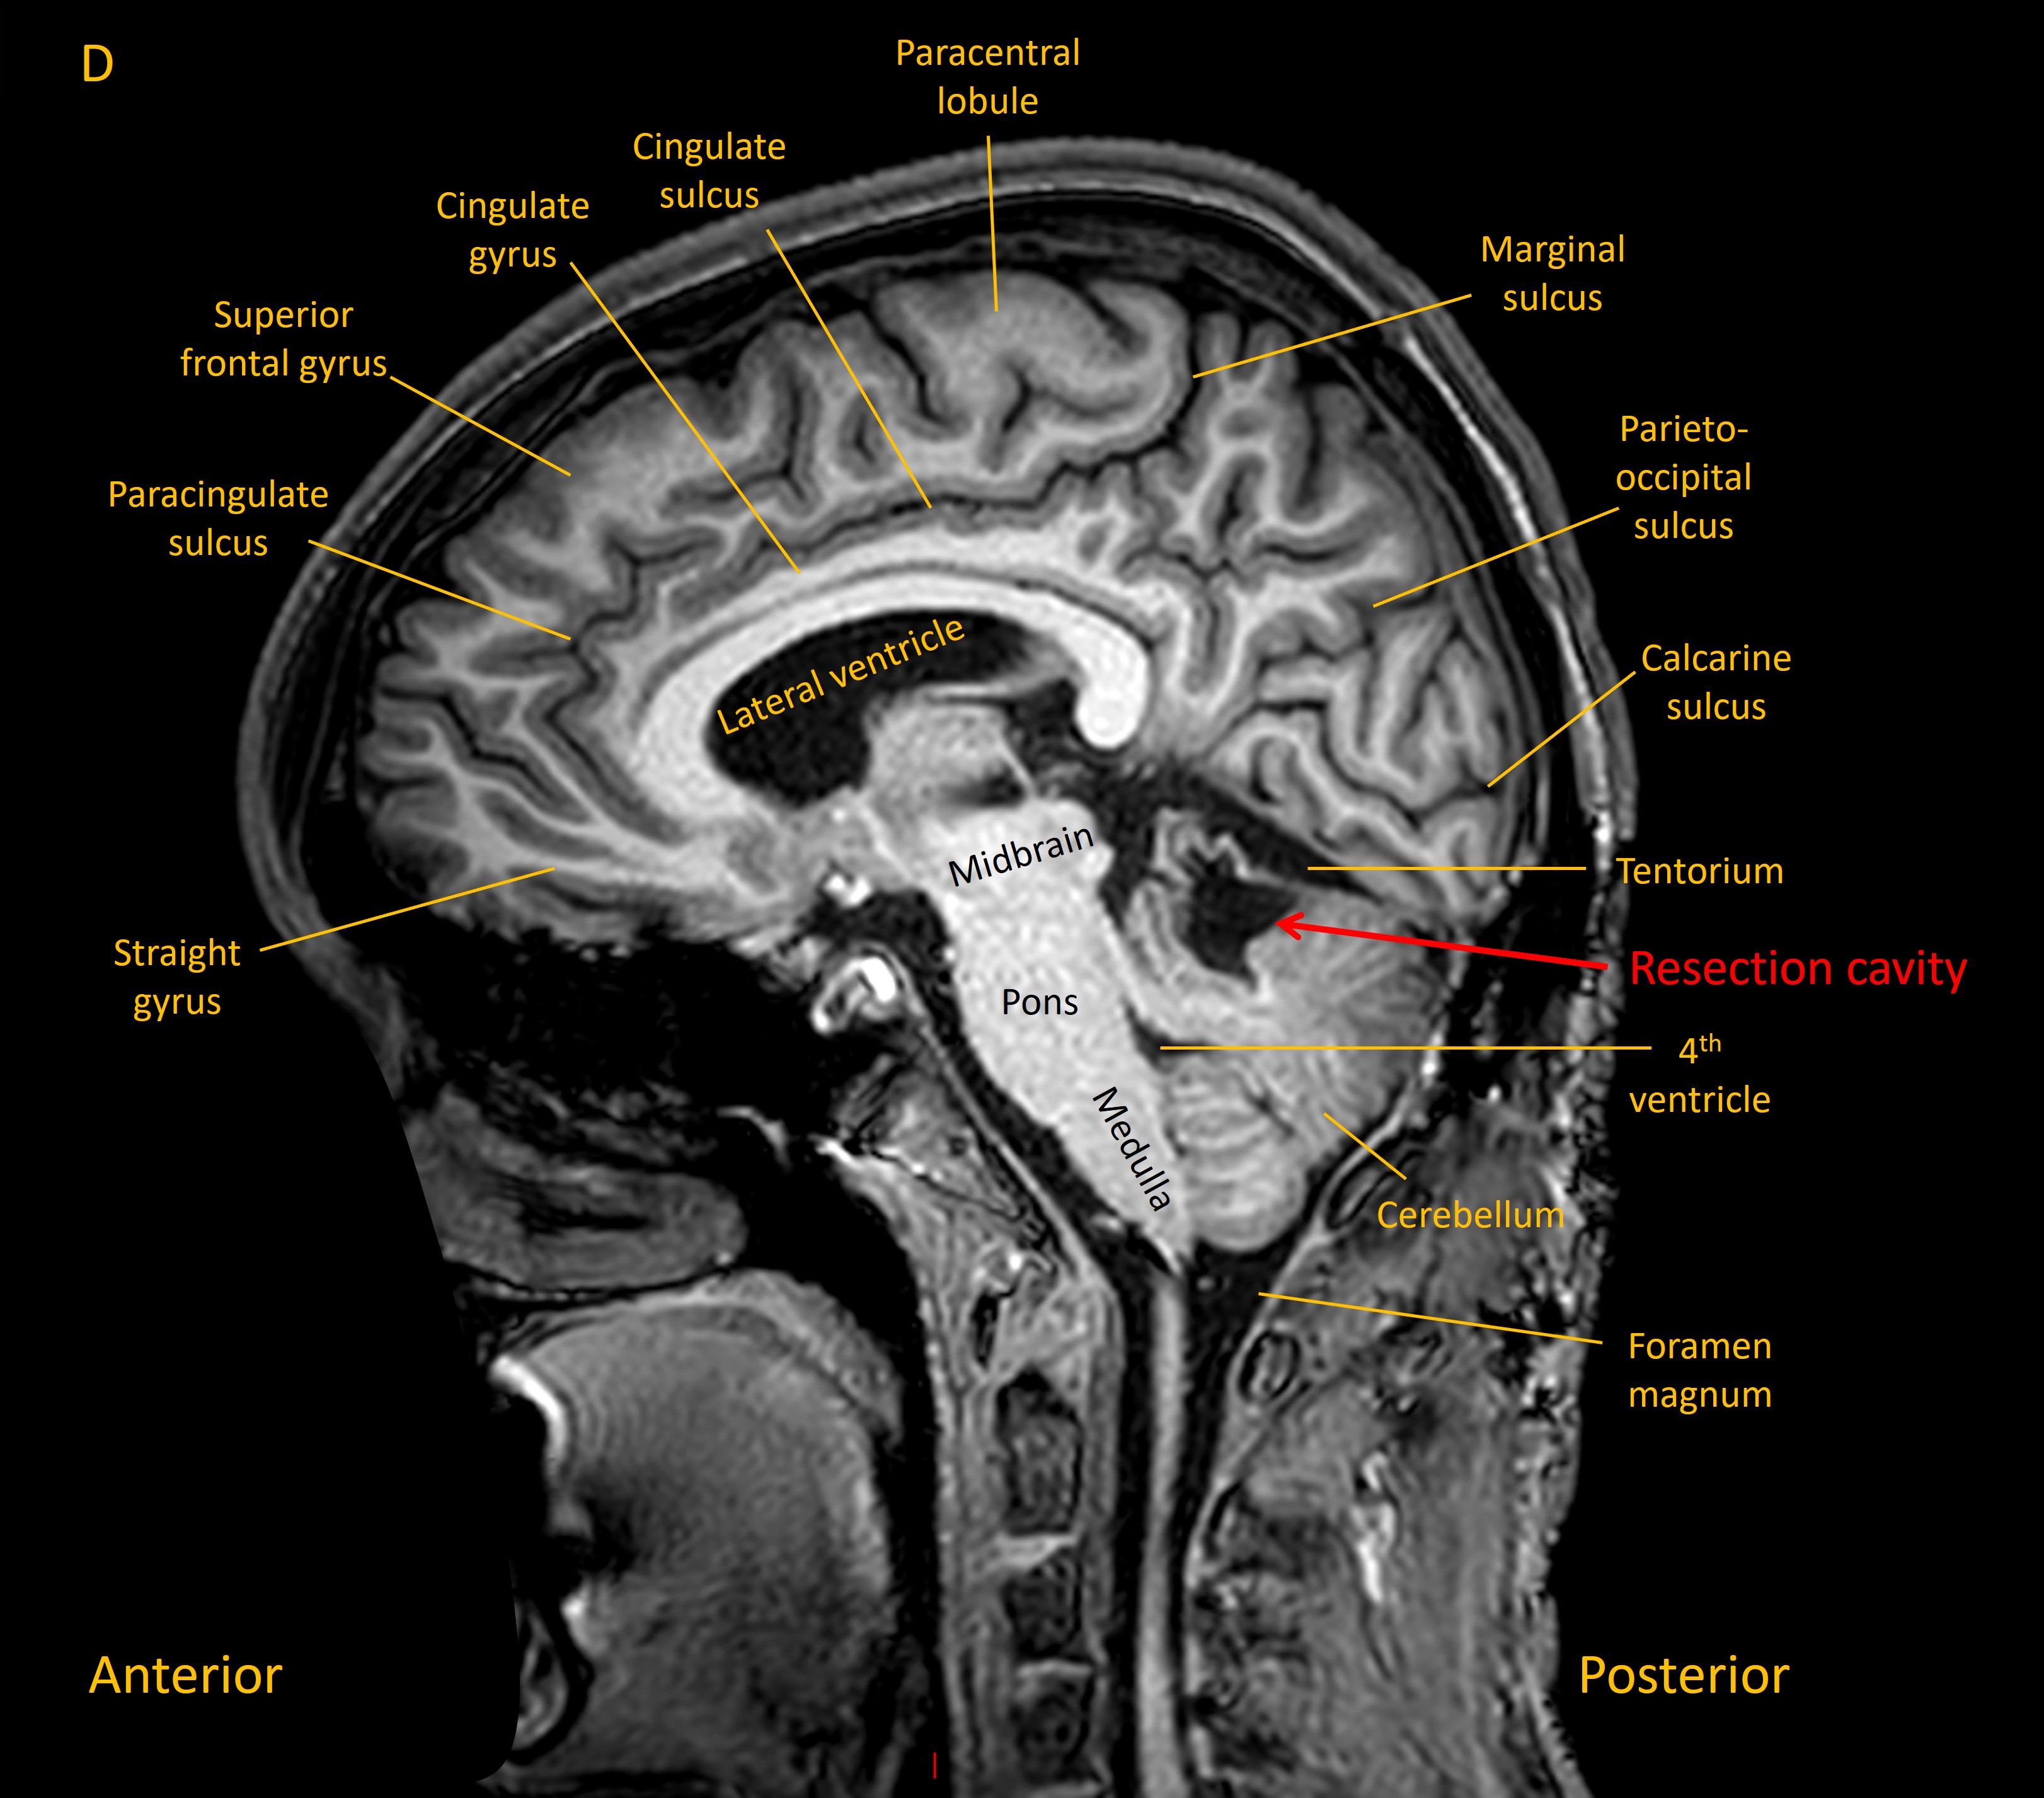

MRI showed a lesion in the right cerebellar hemisphere, with appearances suggestive of a recent haemorrhage surrounding an underlying lesion - shown on the sagittal T1 and axial T2 MRI images below: .

Sagittal MRI

He experienced gradual recovery in the following months, though still had some residual right upper limb ataxia on examination at follow-up 6 months later. A sagittal T1 MRI is shown below, with the resection cavity visible.